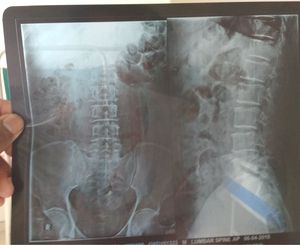

What's your diagnosis??

Iliac fracfure